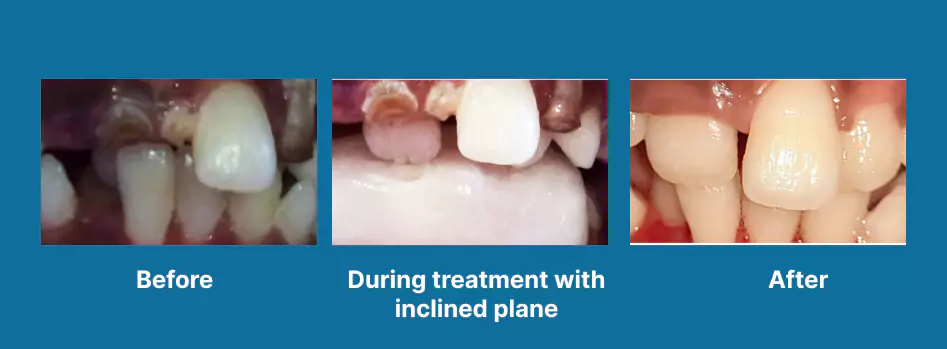

Surgical Orthodontics

Orthodontics

Space Maintainers